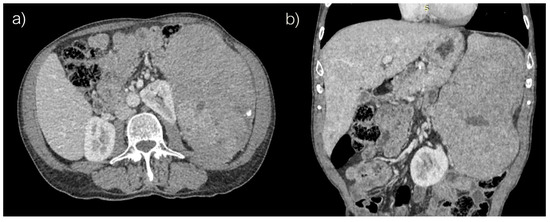

Computed tomography revealed voluminous spleen, an inhomogeneous parenchymal structure with an extensive heterodense lesion with irregular hypodense zones and a post-contrast viable solid component. Peripheral smaller punctiform nodular calcifications were also detected (Figure 1).

Figure 1. Abdominal computed tomography, (a) axial and (b) coronar scans.